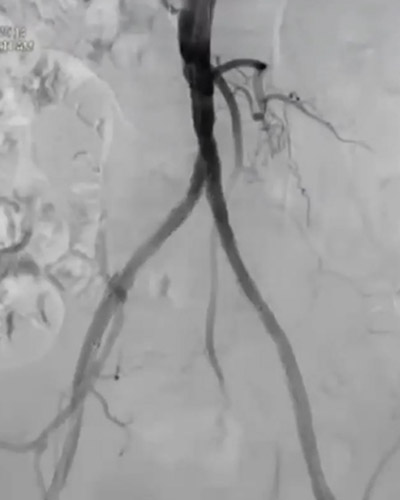

その後、Senri 6-40mmでポスト拡張。動脈瘤部も造影剤の染み出しもなく終了した(図8)。